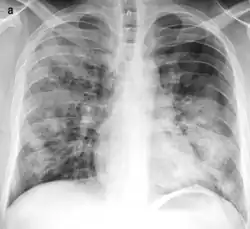

X-ray of bronchopneumonia: multifocal lung consolidation bilaterally.[3]